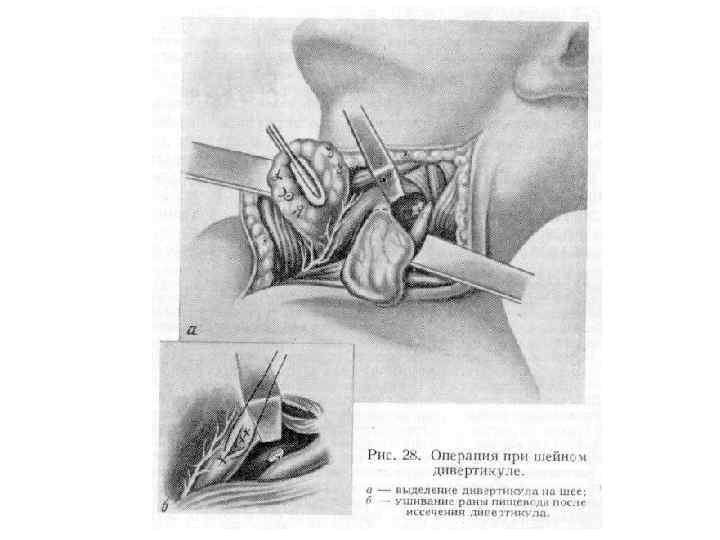

Хирургические доступы к пищеводу • Шейный доступ v Воротникообразный разрез на передней поверхности шеи v Косой разрез Разумовского по переднему краю левой грудиноключично-сосцевидной мышцы • Показания. Удаление инородных тел, глоточнопищеводные дивертикулы, околопищеводные абсцессы и верхнегрудинные медиастиниты.

Хирургические доступы к пищеводу • Шейный доступ v Воротникообразный разрез на передней поверхности шеи v Косой разрез Разумовского по переднему краю левой грудиноключично-сосцевидной мышцы • Показания. Удаление инородных тел, глоточнопищеводные дивертикулы, околопищеводные абсцессы и верхнегрудинные медиастиниты.

• Техника. Больного укладывают на спину с подложенным под плечи валиком, голову запрокидывают и поворачивают вправо. Разрез кожи по переднему краю грудино-ключичнососцевидной мышцы от вырезки грудины до уровня верхнего края щитовидного хряща. Послойно рассекают кожу, подкожную клетчатку, поверхностную фасцию шеи, подкожную мышцу шеи, влагалище грудино-ключично-сосцевидной мышцы вскрывают вблизи переднего края, мышцу оттягивают крючком Фарабефа латерально. Рассекают внутреннюю пластинку грудино-ключично -сосцевидной мышцы и лопаточно-ключичную фасцию шеи.

• Техника. Больного укладывают на спину с подложенным под плечи валиком, голову запрокидывают и поворачивают вправо. Разрез кожи по переднему краю грудино-ключичнососцевидной мышцы от вырезки грудины до уровня верхнего края щитовидного хряща. Послойно рассекают кожу, подкожную клетчатку, поверхностную фасцию шеи, подкожную мышцу шеи, влагалище грудино-ключично-сосцевидной мышцы вскрывают вблизи переднего края, мышцу оттягивают крючком Фарабефа латерально. Рассекают внутреннюю пластинку грудино-ключично -сосцевидной мышцы и лопаточно-ключичную фасцию шеи.

• Левую долю щитовидной железы вместе с трахеей и мышцами (грудино-подъязычной, грудинощитовидной) оттягивают и отодвигают кверху и вправо. Перевязывают нижнюю щитовидную артерию, отодвигают кверху лопаточно-подъязычную мышцу (при короткой шее её пересекают). Разъдиняют тупым способом листок внутришейной фасции, обнажают клетчатку пищеводно-трахейной борозды, где проходит левый возвратный гортанный нерв. Стенку пищевода определяют по красному цвету и продольной исчерченности.

• Левую долю щитовидной железы вместе с трахеей и мышцами (грудино-подъязычной, грудинощитовидной) оттягивают и отодвигают кверху и вправо. Перевязывают нижнюю щитовидную артерию, отодвигают кверху лопаточно-подъязычную мышцу (при короткой шее её пересекают). Разъдиняют тупым способом листок внутришейной фасции, обнажают клетчатку пищеводно-трахейной борозды, где проходит левый возвратный гортанный нерв. Стенку пищевода определяют по красному цвету и продольной исчерченности.